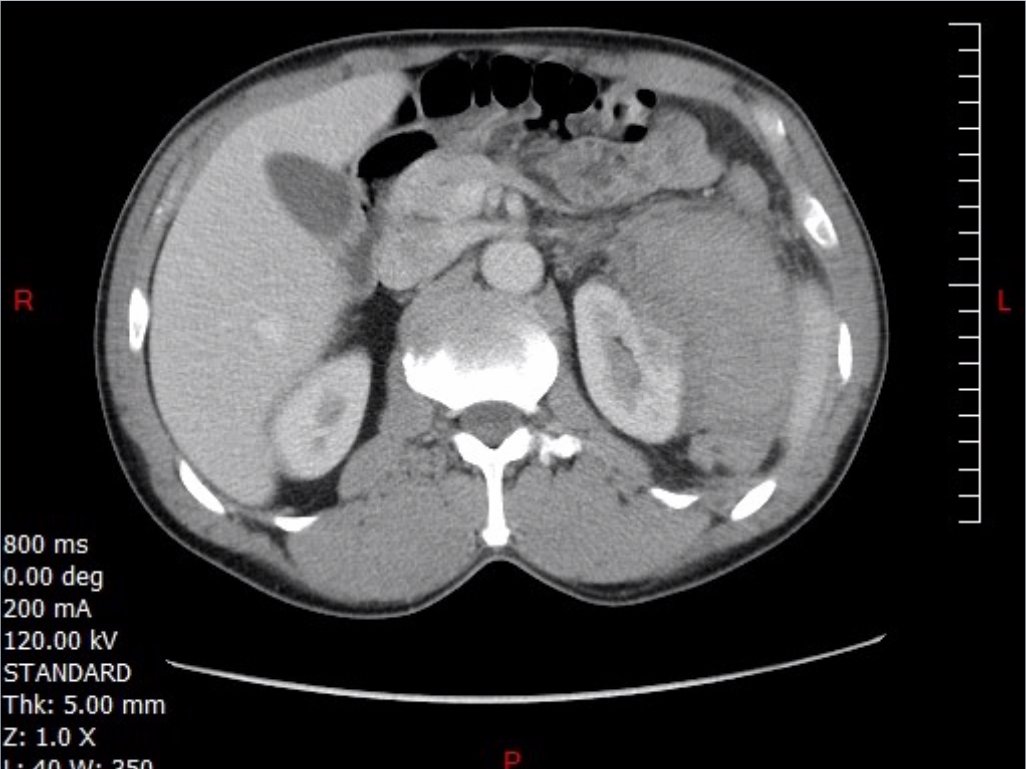

FAST Exam to Diagnose Subcapsular Renal Hematoma

A 49-year-old male presents for evaluation of hematuria and left flank pain after mechanical fall down stairs four days ago. Point-of-care ultrasound (POCUS) focused assessment with sonography in trauma (FAST) exam demonstrated subcapsular renal hematoma. Once a subcapsular hematoma is recognized the provider should keep in mind that this condition may be managed conservatively in patients with two normally functioning kidneys, but may require urgent intervention if the patient is at risk for significant renal disease, such as a single kidney. The use of bedside ultrasound can expedite diagnosis and care for these patients, and allow proper consultants to be contacted early. Some consultants that may need to be consulted include nephrology, urology, and/or internal medicine. This case report emphasizes the utility of the FAST exam for patients presenting for non-acute trauma. The FAST exam can be utilized not only to identify free fluid in the abdomen and pelvis but also to visualize organs and the surrounding tissues for abnormalities after a trauma.